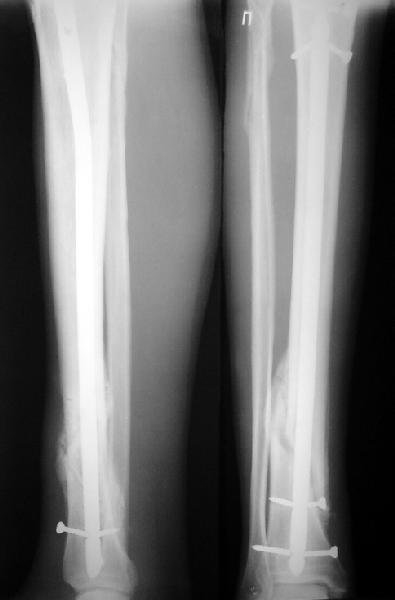

Ok. А также и следующий, в 3 месяца.

Это наглядная демонстрация возможности ранней полной нагрузки при нестабильном по оси повреждении, причем не в самых благоприятных механических условиях - при плохом сопоставлении, со слабым фиксатором.

Как я уже говорил, мы сделали выводы из этого и других подобных случаев. Очевидно, решений проблемы два - либо уменьшить нагрузку, либо увеличить прочность фиксатора. Первое решение работает не со всеми больными, так что пошли по второму пути - мы больше не используем гвозди с запирающими винтами диаметром 4 мм.